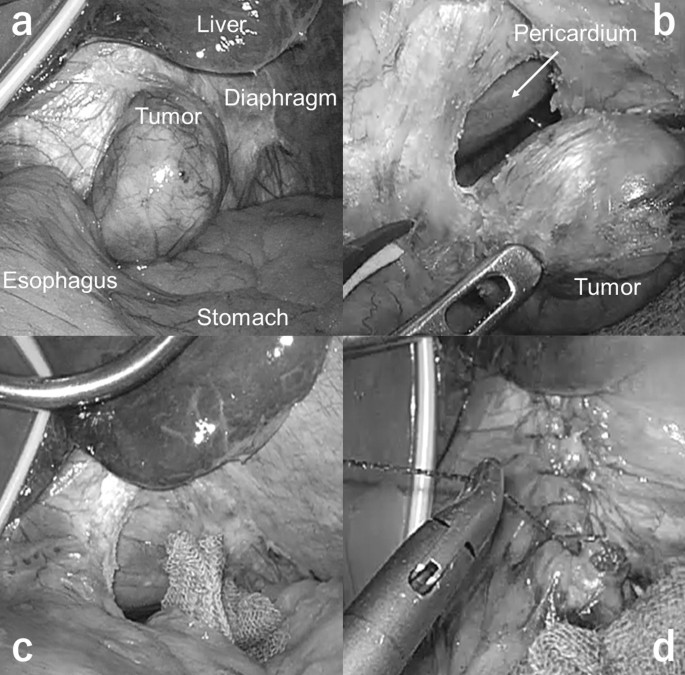

Since the tumor was rather small (less than 3 cm in diameter), we decided to resect the tumor using laparoscopic approach. The tumor was located close to the upper stomach, and we planned to place the trocars using the same arrangement as in upper gastrointestinal surgery. The patient was placed in the supine position with legs apart; the brunt port was inserted from the umbilicus; a 12 mm trocar and three 5 mm trocars were placed in the reverse trapezoid position in the upper abdomen; and the Nathanson’s retractor (HEIWA MEDICAL INSTRUMENTS Co., Ltd. Bofu, Yamaguchi, Japan) was placed in the epigastrium as the liver retractor (Fig. 2). An initial laparoscopic examination revealed a firm, completely encapsulated mass located on the left of the diaphragm (Fig. 3a). Since the tumor was relatively small and visibility was good, we decided to continue with the laparoscopic approach. Partial diaphragmectomy with complete inclusion of the tumor was performed using laparoscopic coagulation shears (Fig. 3b, c). The tumor was packed in a plastic bag and then extracted via the umbilical incision. The defect of the diaphragm was directly closed by a running suture using the 3-0 V-Loc™ absorbable suture (Medtronic plc, Minneapolis, MS, USA) (Fig. 3d). The total operating time was 59 min. The intraoperative blood loss was negligible. A video recording of the surgical procedure has been provided in the Additional file 1.

Intraoperative findings. a An exploratory laparoscopy revealed a firm, completely encapsulated mass located on the left diaphragm. b Partial diaphragmectomy was performed using laparoscopic coagulation shears. c Partial diaphragmectomy including the tumor was completed. d The defect of the diaphragm was directly closed with an absorbable suture